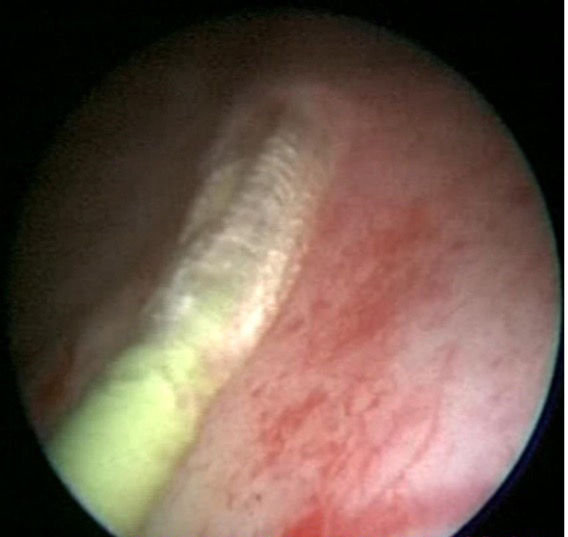

对于绝大多数输尿管狭窄,经尿道输尿管镜下高压球囊扩张术是首选的微创治疗方法。该技术无手术切口,对长度<75px的输尿管狭窄效果尤佳。本院采用质量最佳的进口的BARD输尿管扩张球囊导管(医保覆盖),扩张压力为同类最大,可达30个大气压,扩张成功率高。